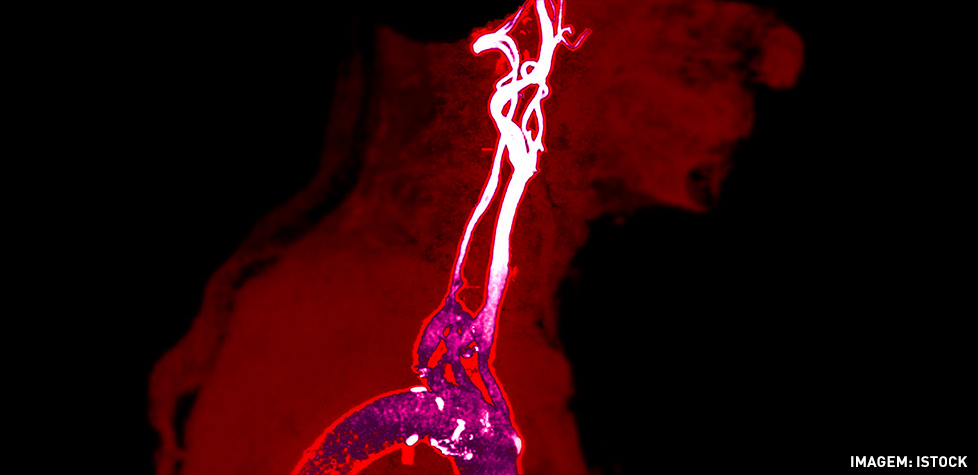

As artérias carótidas são as duas principais artérias do pescoço, que partem do coração e fornecem ao cérebro sangue rico em oxigénio. Com a idade, vai ocorrendo acumulação de placas de ateroma (acumulação de gordura, processo denominado aterosclerose) no interior das artérias carótidas, o que pode levar ao seu estreitamento e redução da facilidade com que o sangue circula. A este fenómeno - que pode ocorrer numa ou em ambas as artérias - chama-se estenose da carótida. Habitualmente, a acumulação de placa ocorre na zona em que a artéria carótida bifurca.